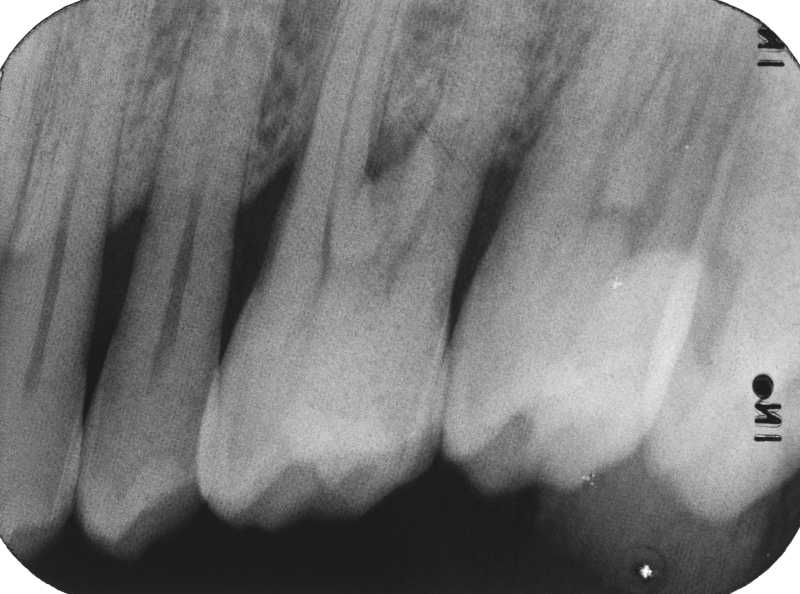

Dental Radiography Film Faults. Quiz 1

Dental Radiography Film Faults. Quiz 1 Enhanced Dental CPD Online Dental Radiograph Quiz test your knowledge of the history and advancements in dental radiography! test your dental radiograph knowledge! discover the improvements in exposure time and film quality, and see how far we've come in capturing accurate dental images. quiz yourself with questions and answers for dental radiology practice test, so you can be ready for test day. . Dental Radiograph Quiz.